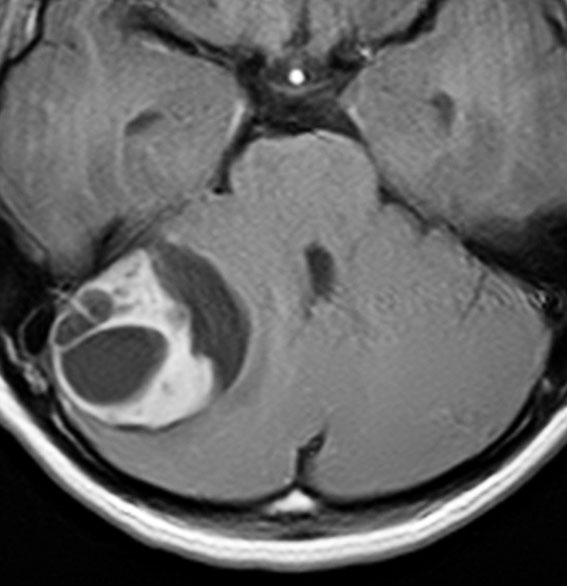

7歳児の小脳半球にある標準リスクの髄芽腫です。画像を一見すればこの髄芽腫は治るであろうと予測します。

手術で完全摘出し,退形成性髄芽腫の病理診断で,脳脊髄照射と局所照射54グレイ,シスプラチンベースの化学療法を6コース加えましたが,半年後に激しい播種再発を生じました。